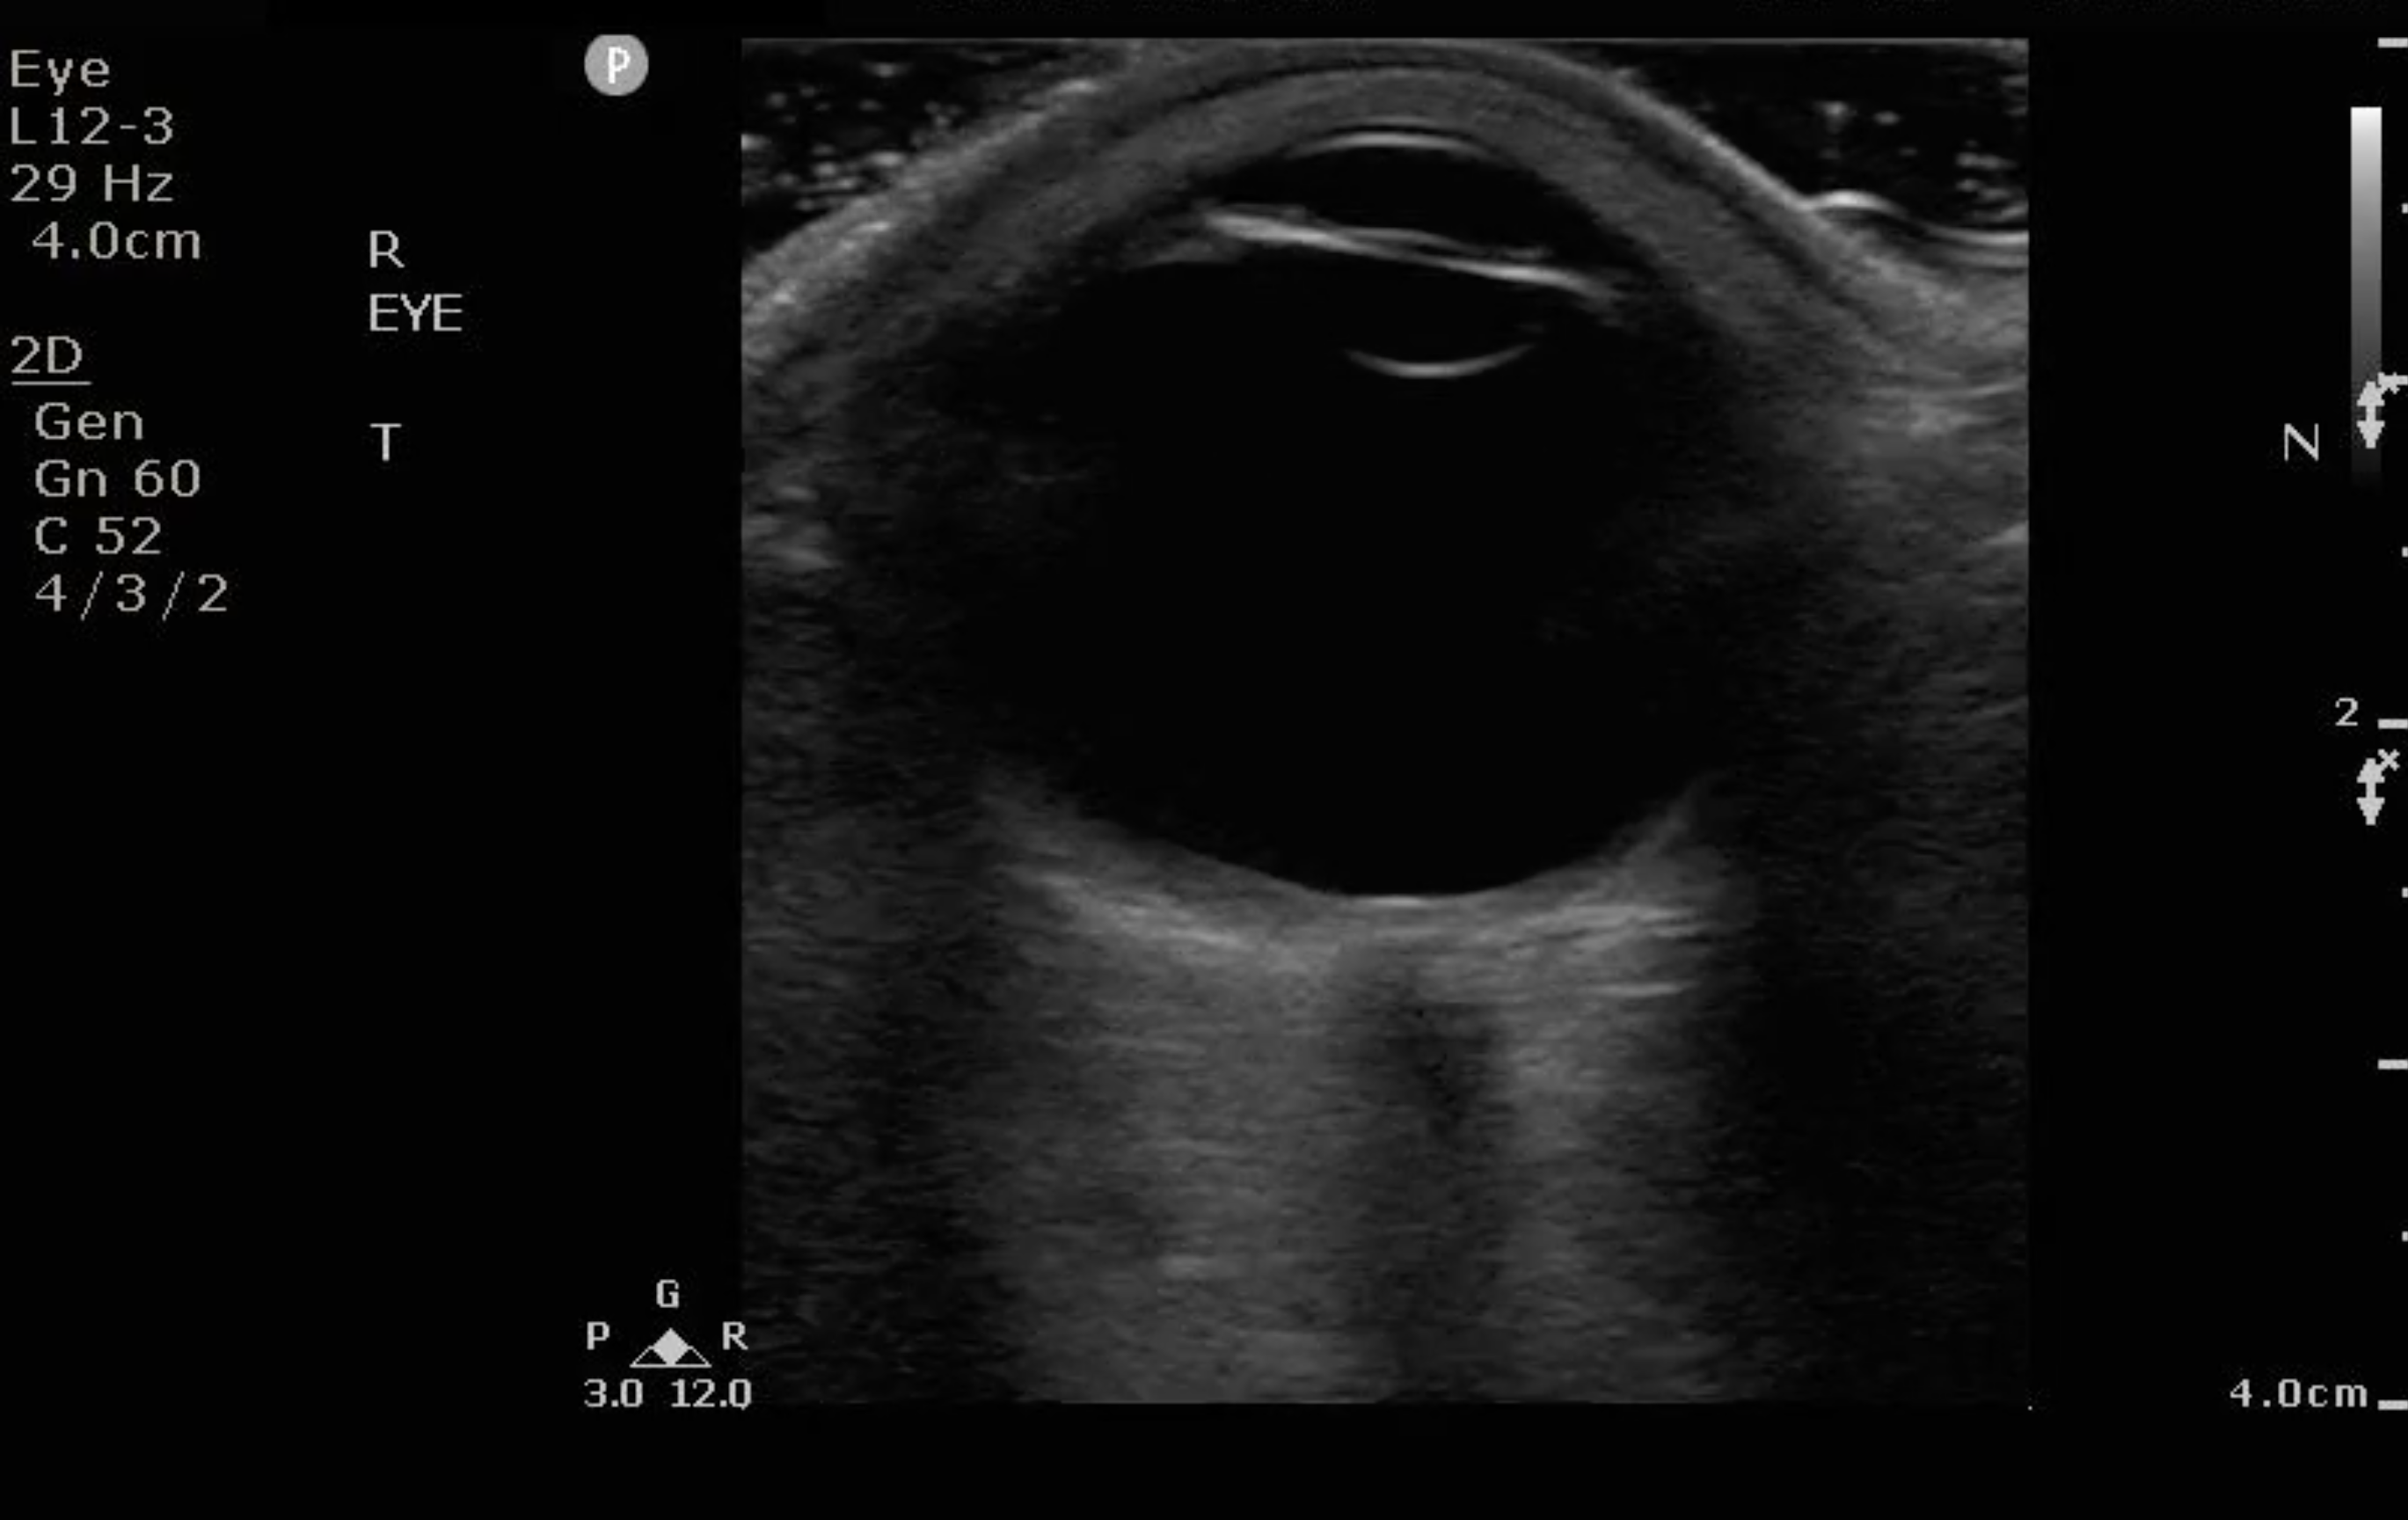

Figure 1. Sonographic eye anatomy

Normal Findings

- Because the ocular chamber is fluid-filled, under ultrasound, it will appear as a round, anechoic structure.

- The most anterior structure seen, after the layer of ultrasound gel, is the eyelid.

- Just deep to the eyelid is the cornea and the anterior chamber. If too much pressure is applied during the ocular ultrasound examination, the anterior chamber may become compressed. It is important to avoid applying direct pressure to the eyelid.

- If the patient attempts to look down during the exam, you may be able to visualize the iris and pupil.

- The lens appears as a hyperechoic, curved line, located deep to the iris. If the patient has undergone cataract surgery, you may see two thin, hyperechoic parallel lines instead of the concave hyperechoic line.

- Normal vitreous humor will appear anechoic.

- The vitreous, retina, and choroid are located along the inside of the globe. Normally, you cannot differentiate one from the other.

- The most far field identifiable structure is the optic nerve. The parallel hyperechoic lines are the optic nerve sheath, since the optic nerve is hypoechoic and nondistinctive.

- Figure 3. Ultrasound image of a normal eye.